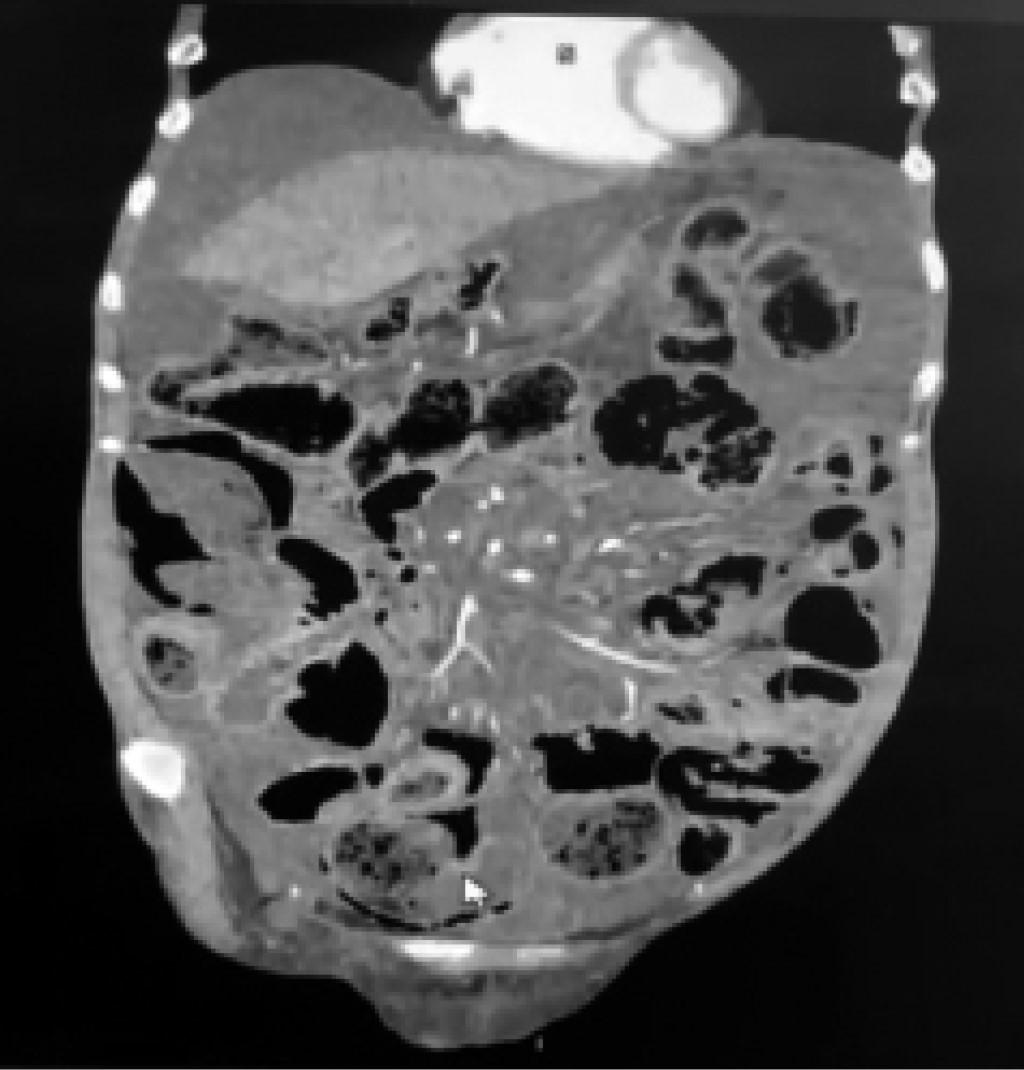

We present the case of a 61-year-old female patient who came to the emergency department with distension, intense and diffuse abdominal pain, intolerance to oral intake, and nausea leading to vomiting with food characteristics of a week's evolution with sudden exacerbation in the last day. As important personal history, she was diagnosed with systemic sclerosis in treatment with immunomodulators, primary hypothyroidism, and chronic liver disease under study, which required therapeutic paracentesis a year ago. The physical examination revealed an afebrile and conscious patient with a globose abdomen tympanic to percussion, decreased peristalsis, pain on deep palpation in the four quadrants, without evidence of peritoneal irritation; no masses or tumors were palpated, there was no ascites fluid under tension, and rectal examination showed no alterations. Laboratory studies were requested on admission without significant alterations, and an ultrasound did not show conclusive changes, with little perihepatic ascites fluid. Conservative management was started with fasting, antibiotic therapy with a double scheme (ciprofloxacin plus metronidazole), and placement of nasogastric tube without exit of food or fecal material through it, without data of improvement, with diaphoresis and progression of abdominal pain, so it was decided to perform a contrasted computerized tomography scan of the abdomen, where air and free liquid in the cavity with high suspicion of intestinal perforation was visualized (Figures 1 and 2). The surgical findings were free air in the abdominal cavity with cystic intestinal pneumatosis of benign origin in the entire small intestine, scarce ascites fluid, and no associated intestinal perforation data (Figure 3). Given this situation, the diagnosis of intestinal pneumatosis was proposed. The evolution was favorable after the three-day intervention with analgesic treatment, antibiotic therapy, and intestinal rest. After six days of remission of the clinical picture, without complications, the patient was discharged and sent to the general surgery outpatient clinic for continued monitoring.

Figure 3